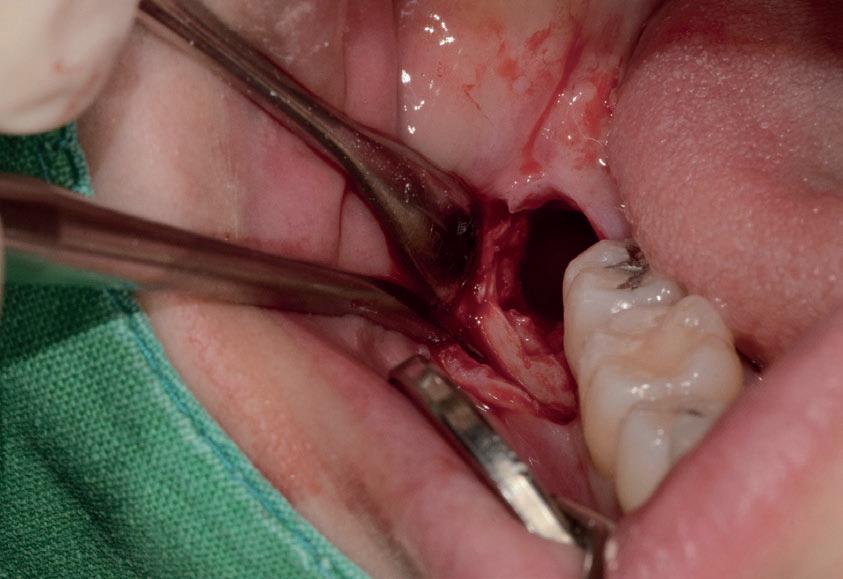

L’estrazione di un dente del giudizio incluso orizzontalmente, sfruttando questa tecnica con il manipolo dritto, richiede un’ulteriore rimozione di struttura dentale e di osso. Figg. 180-183

Per questo motivo, il lembo deve essere esteso fino al primo molare e bisogna avere una visione del sito chirurgico adeguata. Più il dente è inclinato orizzontalmente più la rimozione di osso vestibolare è necessaria.

Solitamente viene utilizzata una fresa a fessura dritta da manipolo per sezionare le radici, ma è preferibile usare una fresa rotonda laddove c’è la necessità di rimuovere l’osso alveolare attorno alla corona, come mostrato in fotografia. Figg. 184-187

In questo caso la separazione del periostio e la rimozione di osso vestibolare è quasi inevitabile per estrarre il #38.

Figg. 180-187 - Un caso di un’estrazione di un dente del giudizio, utilizzando il manipolo dritto. Fig. 180 Fig. 181 Fig. 182 Fig. 183 Fig. 184 Fig. 185 Fig. 186 Fig. 187